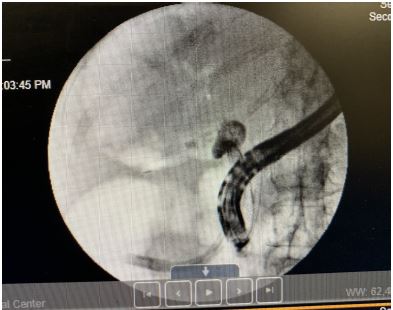

An Endoscopic Retrograde Cholangiopancreatography (ERCP) performed on July 10, 2024, as a possible diagnostic and therapeutic management for obstructive jaundice. The ERCP findings indicated a large unclear tubular structure where the cystic duct should be, with no identifiable gallbladder. The contrast study confirmed the possibility of an obstructed gallbladder versus gallbladder aplasia. The ERCP highlighted significant dilation of the bile ducts, consistent with the earlier CT findings.

Figure 3: Endoscopic retrograde cholangiopancreatography (ERCP).

Given our patient’s presentation, as well as imaging findings, our preliminary diagnosis of acute on chronic cholecystitis warranted laparoscopic cholecystectomy, done on July 3rd, to definitively manage the disease and prevent future biliary tree obstruction. Intraoperatively, direct evidence of gallbladder aplasia was confirmed. The initial assumption of the surgical team was an «extremely contracted gallbladder and fused with the common bile duct,» making separation impossible. On further exploration, a “tubular structure» where the cystic duct should have been, was identified with a complete absence of a gallbladder. This absence was consistent with the imaging results and the ERCP findings.

The patient’s initial presentation, including symptoms of sepsis and elevated inflammatory markers, was complicated by the rare finding of congenital gallbladder agenesis. The imaging findings from the CT scan and HIDA scan, along with the ERCP results and surgical exploration, collectively confirmed the diagnosis. The CT scan showed biliary ductal obstruction and dilation, while the HIDA scan’s nonvisualization of the gallbladder and the ERCP’s findings of a tubular structure without a gallbladder were consistent with the congenital aplasia. Given the patient has a clinical and paraclinical picture of obstructive jaundice with acute cholangitis, the team decided to conduct an ERCP and circumvent the use of an MRCP to further aid in diagnosis and therapy.